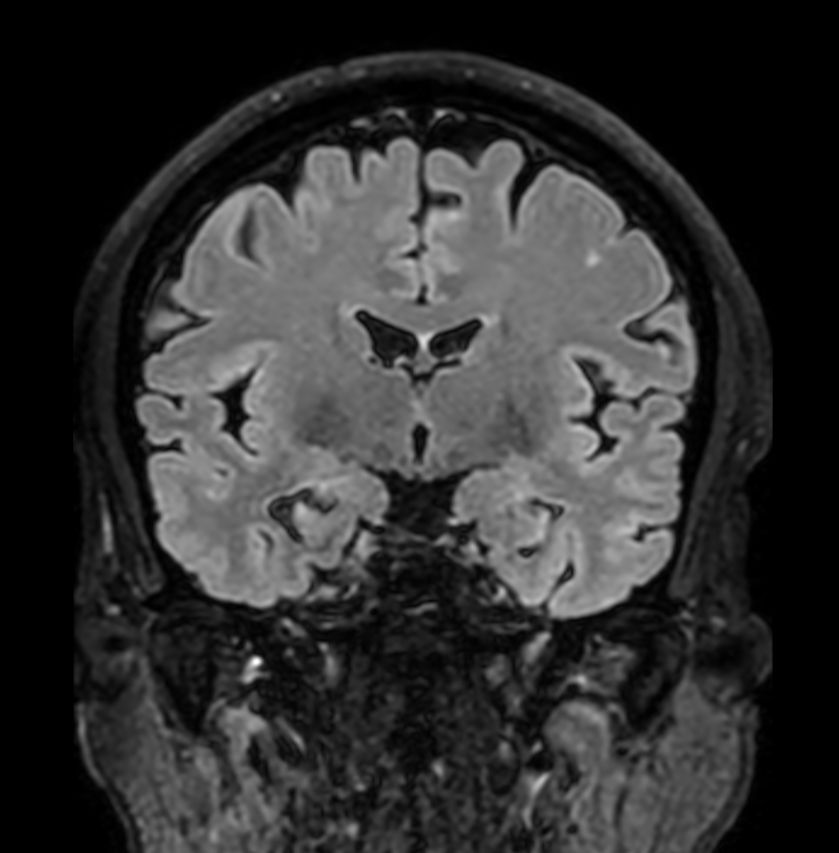

3D T2w FLAIR Compressed SENSE

3D T2w FLAIR (Reformat) Compressed SENSE